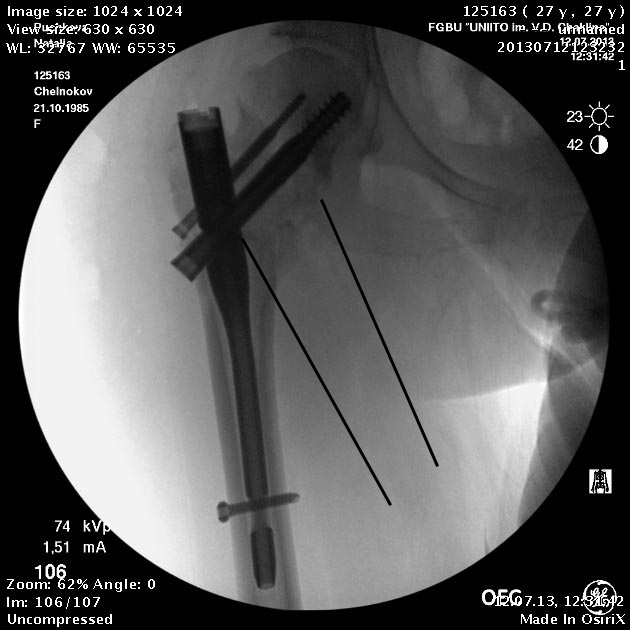

Головка до и во время остеотомии была диафиксирована несколькими

спицами, так что положение ее не менялось. На картинке подрисован

диафиз, был он примерно там. Дистальный винт введен больше на всякий

случай, чтобы дистальный конец гвоздя не болтался. А большой винт

проходит через периферический отломок, так что введение динамического

винта внизу ничего не дало бы.